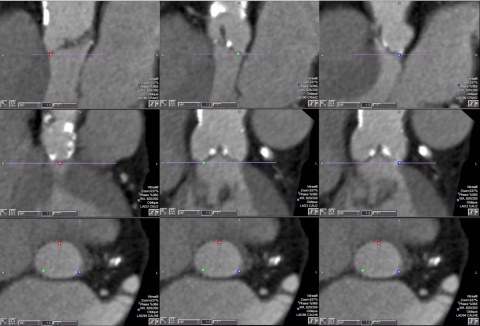

In der retrospektiven Studie wurden 52 konsekutive Patienten eingeschlossen, die zwischen Januar 2012 und Dezember 2013 für eine TAVI evaluiert wurden. Alle Patienten litten unter einer therapiebedürftigen Aortenklappenstenose und die Indikation für eine Intervention wurde nach den gültigen internationalen Leitlinien [1,17] durch eine interdisziplinäre Konferenz gestellt. 38 Patienten erhielten im Verlauf eine TAVI: Hiervon 5 CoreValve™-Prothesen (Medtronic Inc., Minneapolis, MN, USA) über einen transfemoralen Zugangsweg sowie 33 SapienXT™ (Edwards-SAPIEN, Edwards Inc., USA), ebenfalls zu einem Großteil über einen transfemoralen Zugangsweg (n = 28) und in wenigen Fällen über einen transapikalen Zugangsweg (n = 5). Die Prozedur verlief in sämtlichen Fällen primär erfolgreich. Prä-interventionell erfolgte eine MSCT zur Quantifizierung des Aortenklappenanulusdiameters sowie zur Evaluation des Zugangsweges und zur Detektion eventueller Engstellen oder Pathologien, die eine Implantation obsolet hätten werden lassen. Die echokardiographische Evaluation des Aortenklappenaulusdiameters und der Koronaranatomie erfolgte mittels 2- und 3D-Verfahren sowohl transthorakal (TTE), als auch transösophageal (TEE) durch erfahrene Kardiologen. Die CT-Untersuchung fand an einem modernen Mehrschicht-Scanner (Siemens Somatom Sensation 64, Siemens Healthcare, Forchheim, Germany) mit einer Detektorbreite von 4 cm und 64 Auslesezeilen statt. Das Protokoll umfasste die Akquisition eines prospektiv-EKG-gegateten Scans des Herzens unter Fokussierung auf die Aortenklappenebene sowie einen Helical-Scan von Thorax und Abdomen. Beide Untersuchungen erfolgten in der arteriellen Kontrastmittelphase unter Bolus-getriggerter Gabe (CAREBolus™, Siemens Medical, München, Germany) eines jodhaltigen Kontrastmittels (Xenetix® 350, Guerbert AG, Villepinte, France). Das Kontrastmittel wurde mittels Pumpensystem über einen großlumigen intravenösen Zugang mit einer Flussrate von 4 ml/s injiziert. Die Dosis wurde individuell adaptiert. Durch gefilterte Rückprojektion konnten Bilddaten akquiriert werden (Aortenklappenanulusebene: medium smooth kernel B30f, Schichtdicke 0,75 mm, pitch 0,6 mm; Angiographie: smooth kernel B20f, Schichtdicke 0,75 mm, pitch 0,6 mm). Die ursprüngliche CT-Untersuchung wurde durch zwei unabhängige Radiologen mit besondere Expertise auf dem Gebiet der kardio-vaskulären Bildgebung ausgewertet (> 5 Jahre). Zur Befundung dienten triplanare (axiale, sagittale, coronale) Schichten mit einer Schichtdicke von 1 mm im Weichteilkernel. Die Auswertung orientierte sich an den allgemeinen Empfehlungen zur Evaluation eines TAVI-Planungs-CT [15]. Nach Identifikation der Aortenklappenanulusebene mittels kommerziell erhältlicher 3D-Rekonstruktionssoftware (Syngo™ VX91B, Siemens Medical, München) wurden zusätzlich folgende Parameter gemessen: Aortenklappenanulusfläche sowie mittlerer Diameter, Abstand der linken und rechten Koronararterie vom Aortenklappenanulus, mittlerer Aortenbulbusdiameter sowie minimaler Diameter der Aorta thoracalis ascendens. Die Berechnung des mittleren Diameters erfolgte mathematisch aus der Fläche des Aortenklappenanulus entsprechend der aktuellen Literaturempfehlungen [18]. Neben typischen Pathologien lag ein besonderes Augenmerk auf der Betrachtung eventueller Kontraindikationen für eine TAVI, wie Stenosen der Aa. ilacae bzw. aortalen Aneurysmata und Dissektionen. Eventuelle individuelle Anlagevarianten wurden erfasst. Die Reevaluation der CT-Datensätze bediente sich identischer Bilddaten, wurde aber durch zwei unabhängige, gegenüber den ursprünglichen Ergebnissen geblindete Radiologen durchgeführt. Der Unterschied zwischen primärer Auswertung und Reevaluation lag in der zur Bildbearbeitung und Bildauswertung verwendeten Rekonstruktionssoftware. Hierfür wurde die Vital™Vitrea®fX Advanced 6.2 TAVR-Software verwendet, die eine halbautomatisierte Identifikation sowie Messung der Aortenklappenanulusebene bzw. der Aortenklappenanulusfläche ermöglicht. Nach Identifikation der Taschenklappenansätze wurden diese, beginnend mit der rechts-koronaren Klappe, im Uhrzeigersinn virtuell markiert. Nach Validierung der korrekten Identifikation in 3 Raumebenen legte das Programm automatisch eine orthogonale Klappenebene ein (Abb. 1 und 2). Hierauf aufbauend erfolgte die halbautomatische Messung der Flächeninhalte bzw. Abstände, die nur vereinzelt noch manuell nachjustiert werden mussten (Abb. 1).